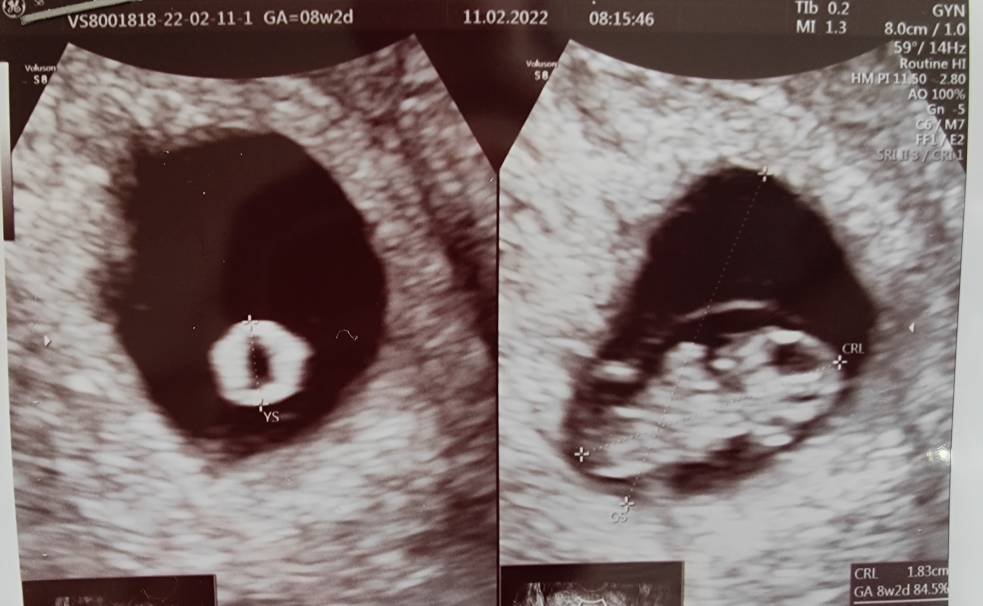

No na chwilę obecną jest ok . Ja żyję od USG do USG . Wczoraj miałam kolejne bo miałam jakiś różowy śluz i już była panika na maksa ale wszystko jest ok . Dzidziuch rośnie , rozwija się tak jak powinien na dzień dzisiejszy . Szczerze to jeszcze to do mnie nie dociera , czuję się zupełnie nie ciążowo. A nauczona doświadczeniem wiem,że jeszcze kilka tygodni nerwowki chociaż,nie wiem czy kiedykolwiek przestanę się denerwować [emoji1745] Zobacz załącznik 1368611